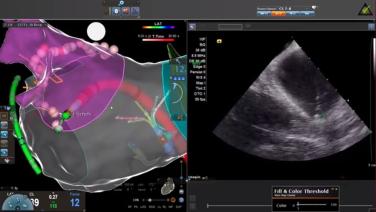

Take your Ablation Workflow to the Next Level with Shephal Doshi, MD